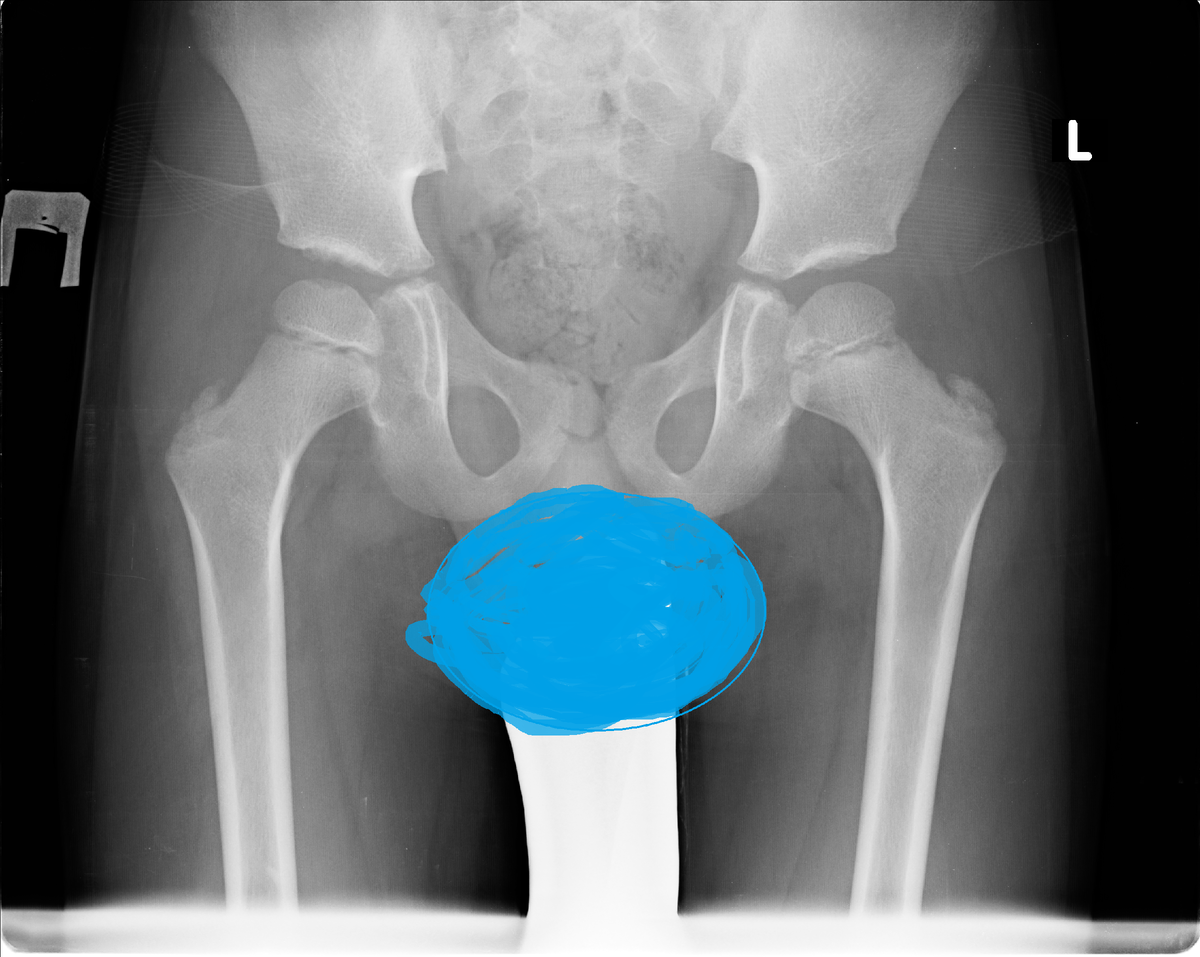

В пятницу вечером информацию на сайте по поводу Егора выложила, на следующий день с утра первым делом принялась читать ответы. Врачи видят только Пертеса или возможно Пертеса, с разной степенью уверенности. Вот куда девается верх головки правого бедра? Но зато меня успокоили насчет онкологии, что вот ее совсем никто не видит, а консультация с онкологом входит в обязательный протокол обследований при данном заболевании. Онкологии нет это хорошо, то что видят Пертеса, не очень, то что вероятно, а не точно, немного обнадеживает. Но в целом ситуация не очень. Правда расстраиваться времени не было. Супчик я с вечера сварила, а вот до второго руки не дошли. Так что закрыла ноутбук и быстренько закинула отвариваться макароны и сосиски. Потом подняла ребятишек. Лизка отправила в школу, Маргариту и Егора лечить глаза (повел дедушка). Сегодня последний день. Все отходили без пропусков 10 дней. А мы с Полей пошли на МСЭ. Все прошло очень доброжелательно, но на удивление долго. Я так долго то

В пятницу вечером информацию на сайте по поводу Егора выложила, на следующий день с утра первым делом принялась читать ответы. Врачи видят только Пертеса или возможно Пертеса, с разной степенью уверенности.

Вот куда девается верх головки правого бедра?

Но зато меня успокоили насчет онкологии, что вот ее совсем никто не видит, а консультация с онкологом входит в обязательный протокол обследований при данном заболевании.

Онкологии нет это хорошо, то что видят Пертеса, не очень, то что вероятно, а не точно, немного обнадеживает. Но в целом ситуация не очень.